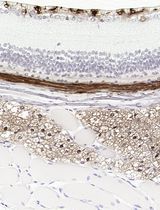

Asthma is a complex phenotype that involves multiple mechanisms, including adaptive and innate immunity as well as physiological and mechanical changes in the airways. In the models of asthma induced by sensitization and aerosolized allergen exposure in the absence of adjuvant, mast cells facilitate the development of in ammation and airway hyper-responsiveness. This model is useful to analysis of function of mast cells in AHR.